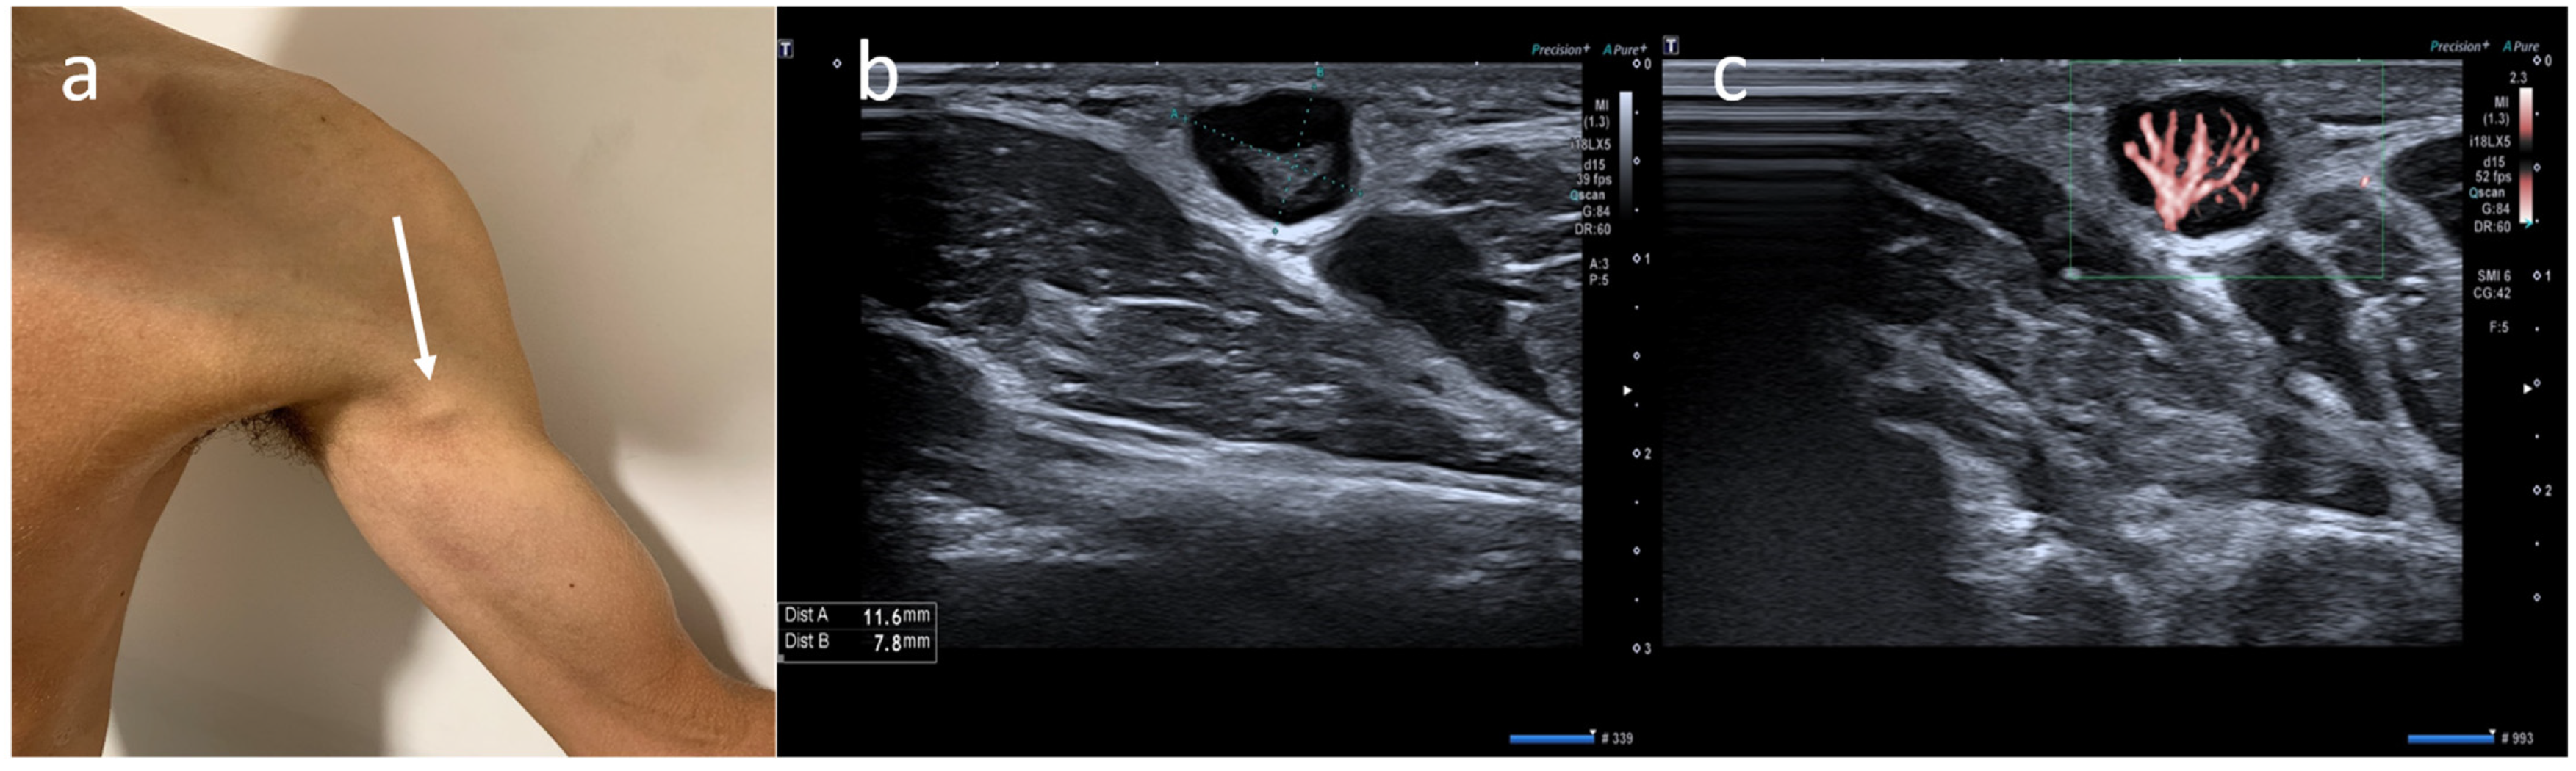

- Cocco, G.; Pizzi, A.D.; Fabiani, S.; Cocco, N.; Boccatonda, A.; Frisone, A.; Scarano, A.; Schiavone, C. Lymphadenopathy after the Anti-COVID-19 Vaccine: Multiparametric Ultrasound Findings. Biology 2021, 10, 652. [Google Scholar] [CrossRef] [PubMed]